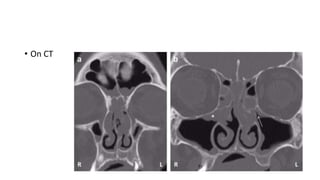

• On CT